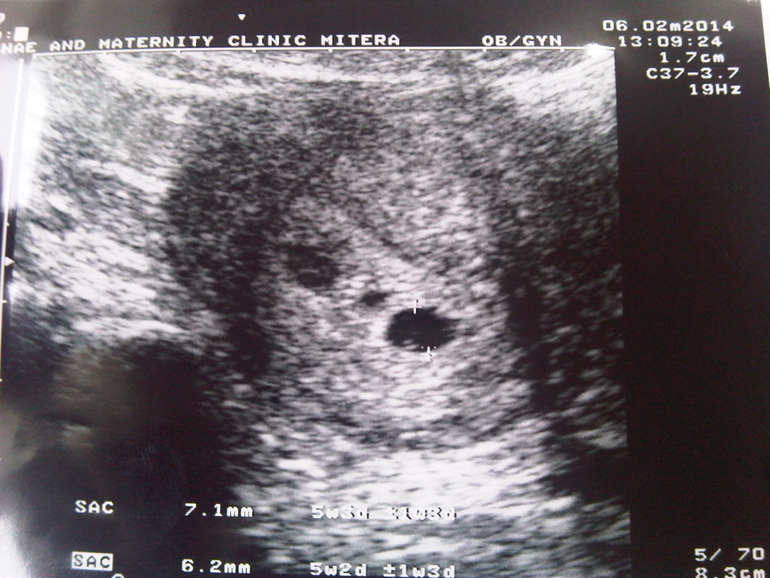

УЗИ двухплодной беременности на 5 неделе: Подборка изображений

Раздел: Калейдоскоп образов